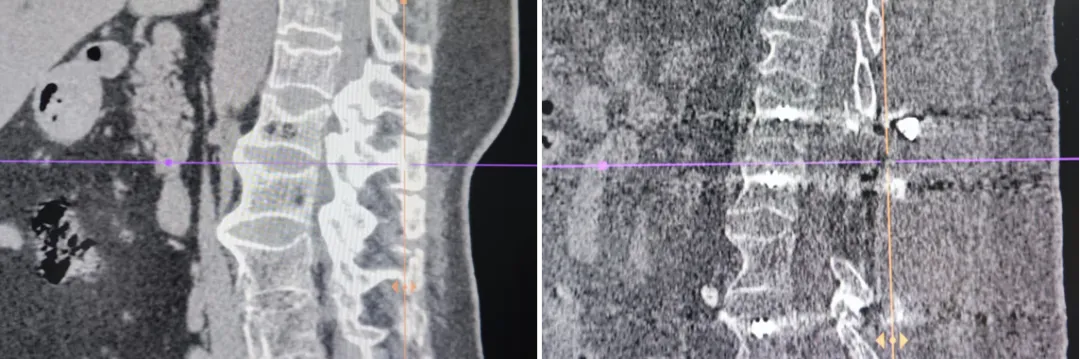

【特色诊疗】新疆医科大学第六附属医院脊柱外三科成功救治一名颈椎后纵韧带骨化伴截瘫患者